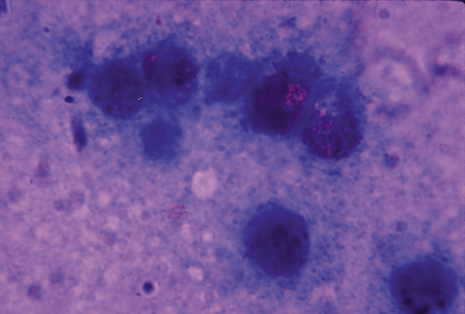

Many forms of uveitis are characterized by specific types of inflammatory cells. Usually, however, one encounters mixtures of cell types in any given specimen, with the relative percentages of lymphocytes and polymorphonuclear leukocytes varying. There may be unusual numbers of eosinophils, or macrophages laden with lens material may be present. Thus, an enumeration of the cells and a careful analysis of their structure can be useful as a diagnostic aid (Figs. 7, 8, 9, 10, 11, 12, 13, 14, 15, 16, 17, 18, 19, and 20). Figure 15 demonstrates eosinophils that were aspirated from the anterior chamber of a patient with Toxocara canis endophthalmitis. Figure 12 demonstrates malignant cell infiltrate from the vitreous, showing the stained presence of monoclonal light chains being elaborated in the cytoplasm. Interleukin-10, detectable in the vitreous of intraocular lymphoma patients, is also directly indicative of both the clinical activity and the number of malignant cells as observed by cytopathology.